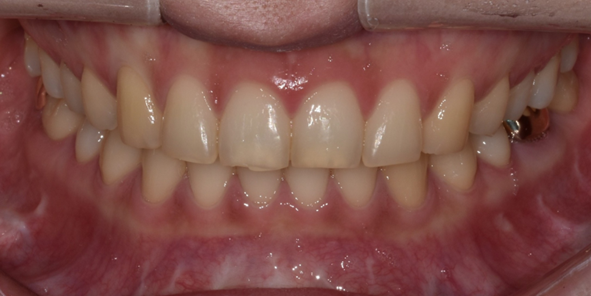

29세 여성

최소삭제 라미네이트

(전) 2022-08-02 (후) 2022-08-11

교정 후 치아 배열은 고르게 개선되었지만 치아 모양과 색상이 마음에 들지 않아 라미네이트 진행하신 환자분인데요.

고른 치아배열로 인해 최소삭제 라미네이트로 시술해드렸던 환자분입니다.